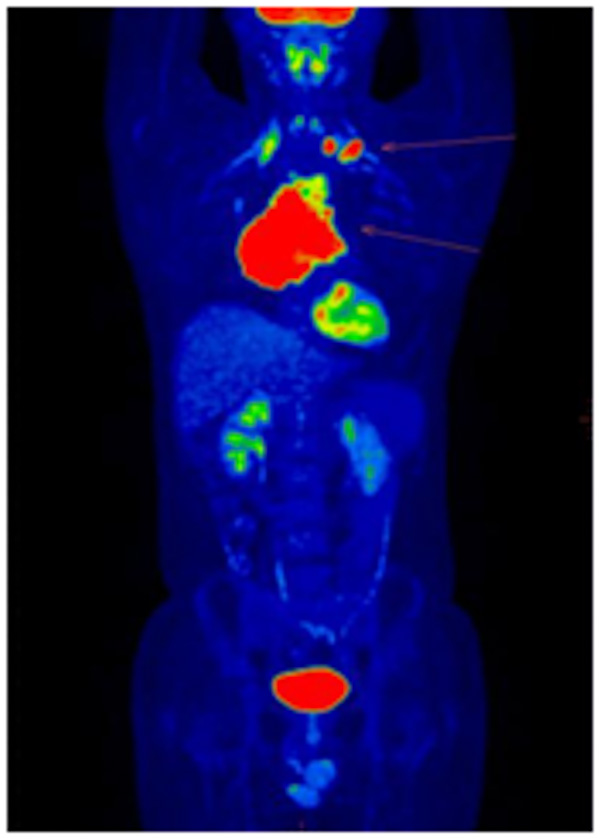

為確定治療方案,了解其他部位是否有淋巴瘤浸潤(rùn),進(jìn)行了PET-CT檢查,患者全身MIP圖一目了然!縱隔巨大腫塊淋巴瘤,左側(cè)鎖骨上窩淋巴結(jié)淋巴瘤浸潤(rùn)。

治療4周期后,患者癥狀好轉(zhuǎn),再次到核醫(yī)學(xué)科行PET/CT顯像檢查,如圖所示。

治療后前上縱隔軟組織較前明顯縮小,仍有腫瘤活性組織存在;雙側(cè)鎖骨上窩、縱隔2組淋巴結(jié)均已吸收、滅活;右側(cè)胸膜及心包稍增厚。治療后病灶較前明顯縮小、減少,極大地緩解了患者相關(guān)臨床癥狀。